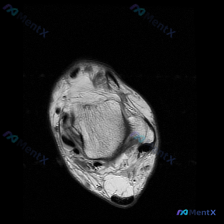

看到这张踝关节MRI,问题问有什么异常,很多人第一反应就是看到软组织积液,但其实背后藏着更关键的问题,我整理一下完整的分析思路给大家。 病例影像基础信息 这是一张踝关节MRI T2序列轴位影像,我们先把所有能看到的征象理清楚: 1. 骨骼结构:影像中心是距骨横截面,皮质骨低信号、骨髓中等信号,骨质轮...

看到这个踝关节MRI的病例,整理了完整的影像资料和分析思路,和大家分享讨论。 病例影像基础信息 这是踝关节MRI T2加权轴位图像,扫描层面为踝关节远端,可见距骨体及周围软组织结构,图像对比度满足观察要求,T2加权像液体呈高信号。 核心影像发现 1. 骨结构:距骨及周围骨性结构骨髓无异常高信号,骨皮...

刚看到这份踝关节MRI读片需求,整理了完整的观察和分析思路分享给大家。 病例基本影像信息 本次读片基于踝关节MRI-T2序列轴位图像,扫描层面为踝关节远端轴位,可清晰辨认胫骨、腓骨、距骨以及后方跟腱等正常解剖结构。T2序列对液体和水肿敏感,正常肌腱韧带应为低信号(黑色),液体/水肿为高信号(白色)。...

刚整理完一份踝关节MRI的读片分析,关于软组织积液的鉴别思路挺典型,分享给大家一起讨论。 病例影像基本信息 这是一份踝关节MRI T2序列轴位影像,扫描层面为距骨体水平,显示踝关节及周围软组织结构: 1. 骨骼表现:距骨及周围骨性结构骨皮质完整,骨髓信号无局灶异常高信号,排除明显骨挫伤、骨折或骨髓水...

刚看到这张踝关节T2轴位MRI,我整理一下影像表现和分析思路,跟大家讨论一下。 病例影像基本信息 这是踝关节轴位T2加权MRI,液体呈高信号(亮白色),骨皮质、肌腱韧带呈低信号(黑色)。 先看基础结构: - 骨性结构:胫骨、腓骨、距骨截面可见,骨髓信号均匀,没有明显骨质破坏或异常骨髓水肿 - 肌腱结...

最近看到一份踝关节MRI的影像分析,整理了整个诊断思路分享给大家,一起讨论下。 病例影像基本信息 这是踝关节轴位T2加权MRI扫描,核心发现整理如下: 1. 骨骼结构:胫骨、腓骨、距骨骨皮质完整,没有骨折线,骨髓信号均匀,无明显弥漫性骨髓水肿 2. 肌腱韧带:内外侧肌腱、跟腱走行正常,信号均匀,无腱...

今天整理了一份踝关节MRI的读片分析,核心问题是影像发现「软组织积液」该怎么判断,分享出来大家一起讨论。 病例影像基础信息 这是一份踝关节轴位T2加权MRI(T2WI)的读片报告,核心信息整理如下: 1. 骨骼结构:胫骨远端、距骨骨髓信号正常,无骨髓水肿、骨质破坏,皮质完整,未见骨折线 2. 关节结...